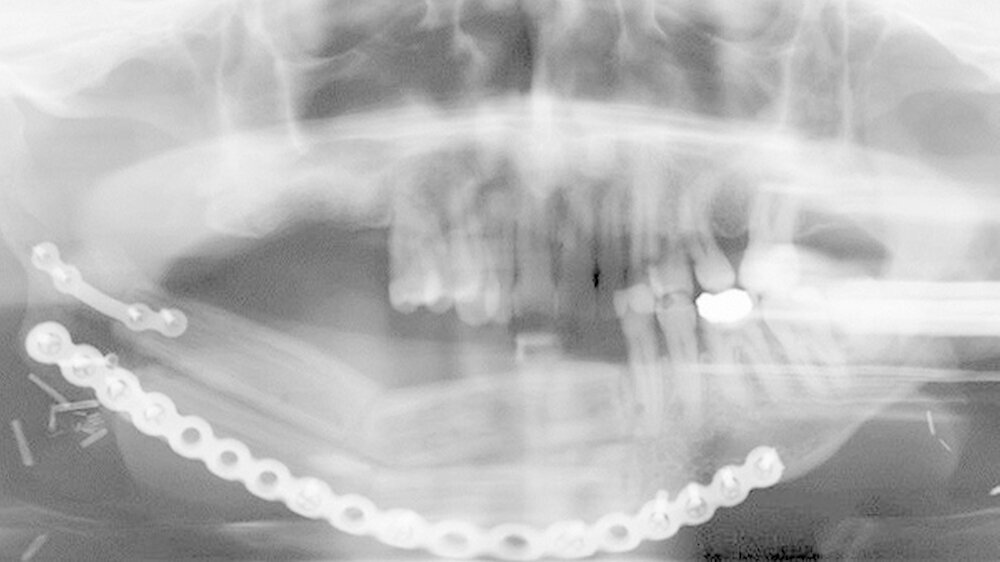

Ein Jahr nach der Exzision des Primärtumors, der begleitenden Radiatio sowie dem mikrochirurgischenAufbau des Unterkieferdefekts stellte sich der Patient erneut vor, um einen Termin zur Entfernung des Osteosynthesematerials zu vereinbaren. Bei dieser Untersuchung bemerkten die Chirurgen eine erhebliche Raumforderung am linken Oberarm, die nach Angaben des Patienten sehr schnellem Wachstum.

Weder das Röntgenbild noch die weitere Untersuchung mit magnetresonanztomografischer Bildgebung gaben eindeutigen Aufschluss. Daraufhin wurde eine Biopsie veranlasst, die die Verdachtsdiagnose einer Metastase des oralen Plattenepithelkarzinoms histologisch bestätigte.